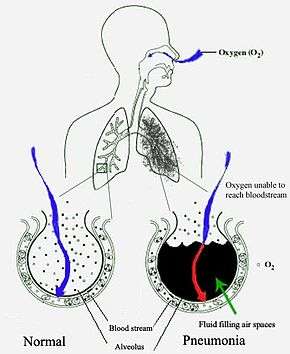

Pneumonia is an inflammatory condition of the lung affecting primarily the microscopic air sacs known as alveoli.[2][3] Typical signs and symptoms include a varying severity and combination of productive or dry cough, chest pain, fever, and trouble breathing, depending on the underlying cause.[4]

Pneumonia frequently starts as an upper respiratory tract infection that moves into the lower respiratory tract.[39] It is pneumonitis (lung inflammation) combined with consolidation (liquid in spaces normally inflated with air).[40]

Most bacteria enter the lungs via small aspirations of organisms residing in the throat or nose.[20] Half of normal people have these small aspirations during sleep.[24] While the throat always contains bacteria, potentially infectious ones reside there only at certain times and under certain conditions.[24] A minority of types of bacteria such as Mycobacterium tuberculosis and Legionella pneumophila reach the lungs via contaminated airborne droplets.[20] Bacteria can spread also via the blood.[21] Once in the lungs, bacteria may invade the spaces between cells and between alveoli, where the macrophages and neutrophils (defensive white blood cells) attempt to inactivate the bacteria.[42] The neutrophils also release cytokines, causing a general activation of the immune system.[43] This leads to the fever, chills, and fatigue common in bacterial pneumonia.[43] The neutrophils, bacteria, and fluid from surrounding blood vessels fill the alveoli, resulting in the consolidation seen on chest X-ray.[44]